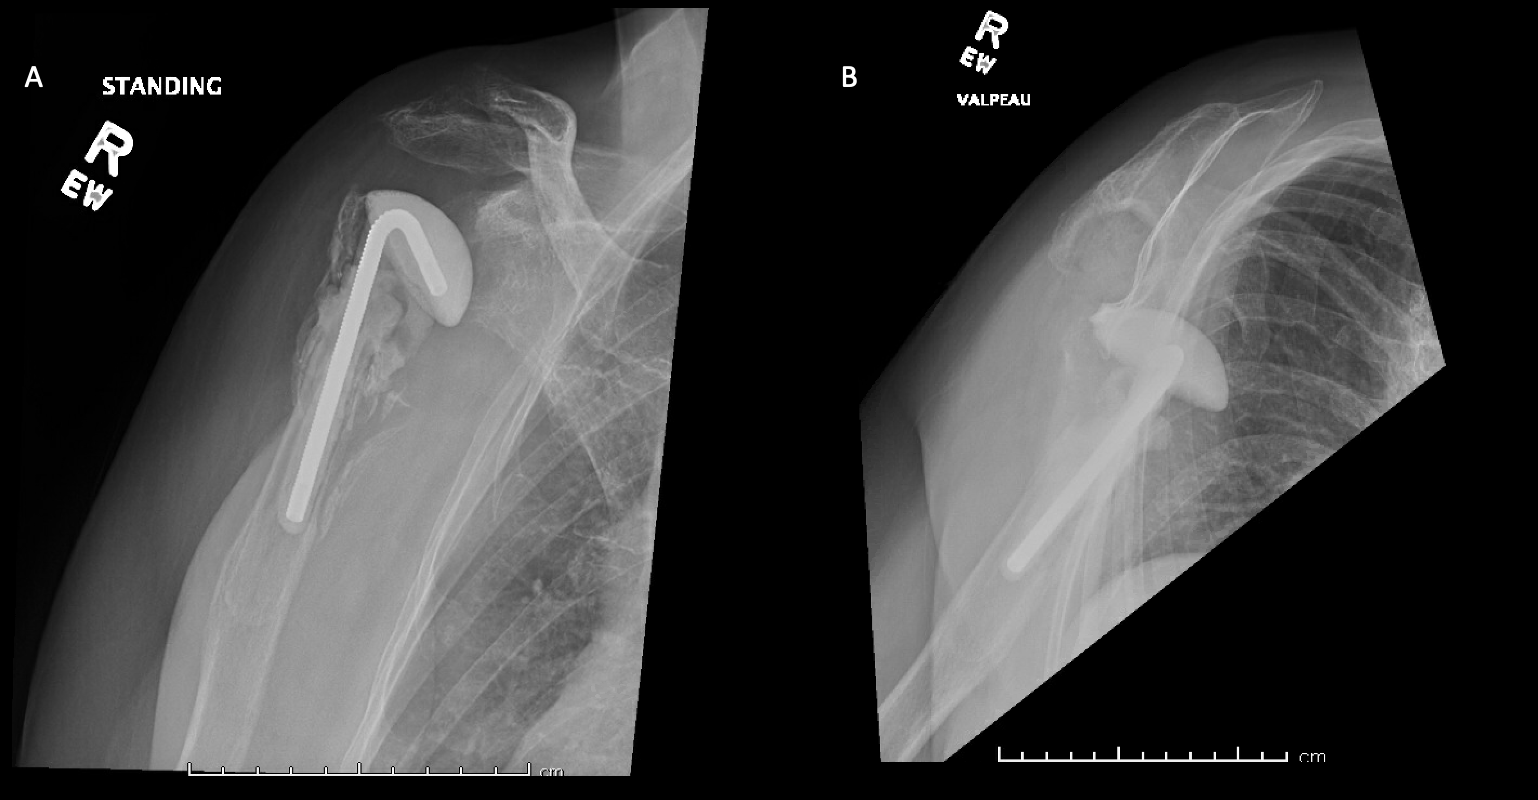

Case 1. At the latest follow-up one-year post-op, patient 1, who had the more extensive humeral exposure, was extremely pleased with the results of the surgery despite occasional pain. She had resolution of an early post-op radial nerve palsy. She could button up her blouse and get her hand to her mouth. Her shoulder and scapular x-rays showed some new radiolucency between the superior aspect of the glenoid prosthetic component and the associated bone cement in the subacromial space (Figure 13). At 2 years post-op she continues to have significant pain relief and has maintained her active range of motion (AROM). Elbow AROM was from 10 to 145 degrees. Shoulder AROM was abduction to 15 degrees and internal rotation allowing the hand to reach the level of L5/S1 vertebrae.

Case 2. At the latest follow-up one-year post-op, the patient expressed that the pre-operative pain had resolved after the operation. Despite this, she stated that if given the option again she would not undergo the surgery because she did not attain the function she expected and felt that her function may have decreased compared to pre-op. Overall stability and alignment were good. On physical exam, she was able to reach within 1 inch from her mouth and had 20 degrees abduction and 5 degrees forward flexion actively. Active elbow flexion was 0 to 120 degrees (Figures 14). At 2 years post-op she had some regression in her pain but accompanied by modestly decreased AROM. Shoulder AROM was 15 degrees abduction, and 5 degrees forward flexion. Elbow AROM was from 0 to 105 degrees of elbow flexion. CT scan showed increased lucency surrounding the humeral component concerning for osteolysis and prosthesis loosening (Figure 14). Blood work at the 2-year mark to investigate the radiolucencies and decreased AROM left us with low suspicion for infection (WBC 5.4, ESR 33, CRP <3.0).